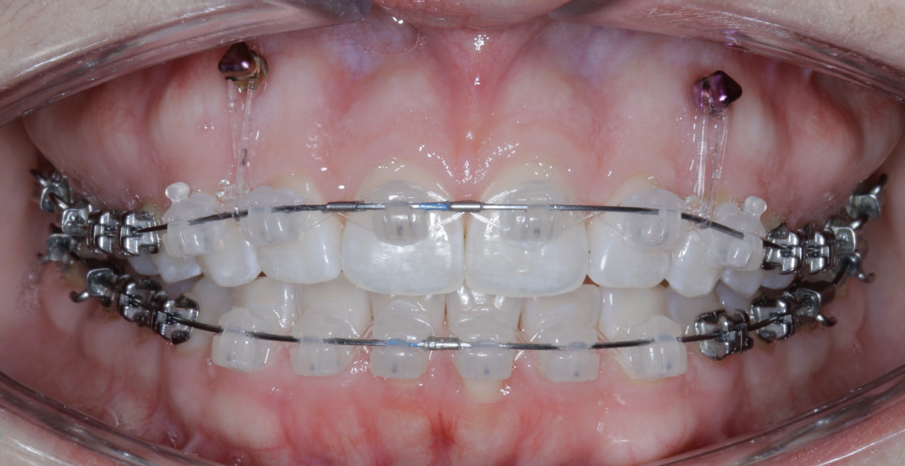

TADs are placed at the second visit with a 14 × 25 mm copper (Cu) and nickel–titanium (NiTi) wire and are tied from the anchor to the wire with an elastic thread (surgical thread; Fig. 6). Once the patient has progressed to larger Cu–NiTi wires and stainless steel, the TADs are tied to the wire using a power chain looped to the wire, or NiTi closing springs, depending on the thickness of the tissue (Figs. 7 & 8).